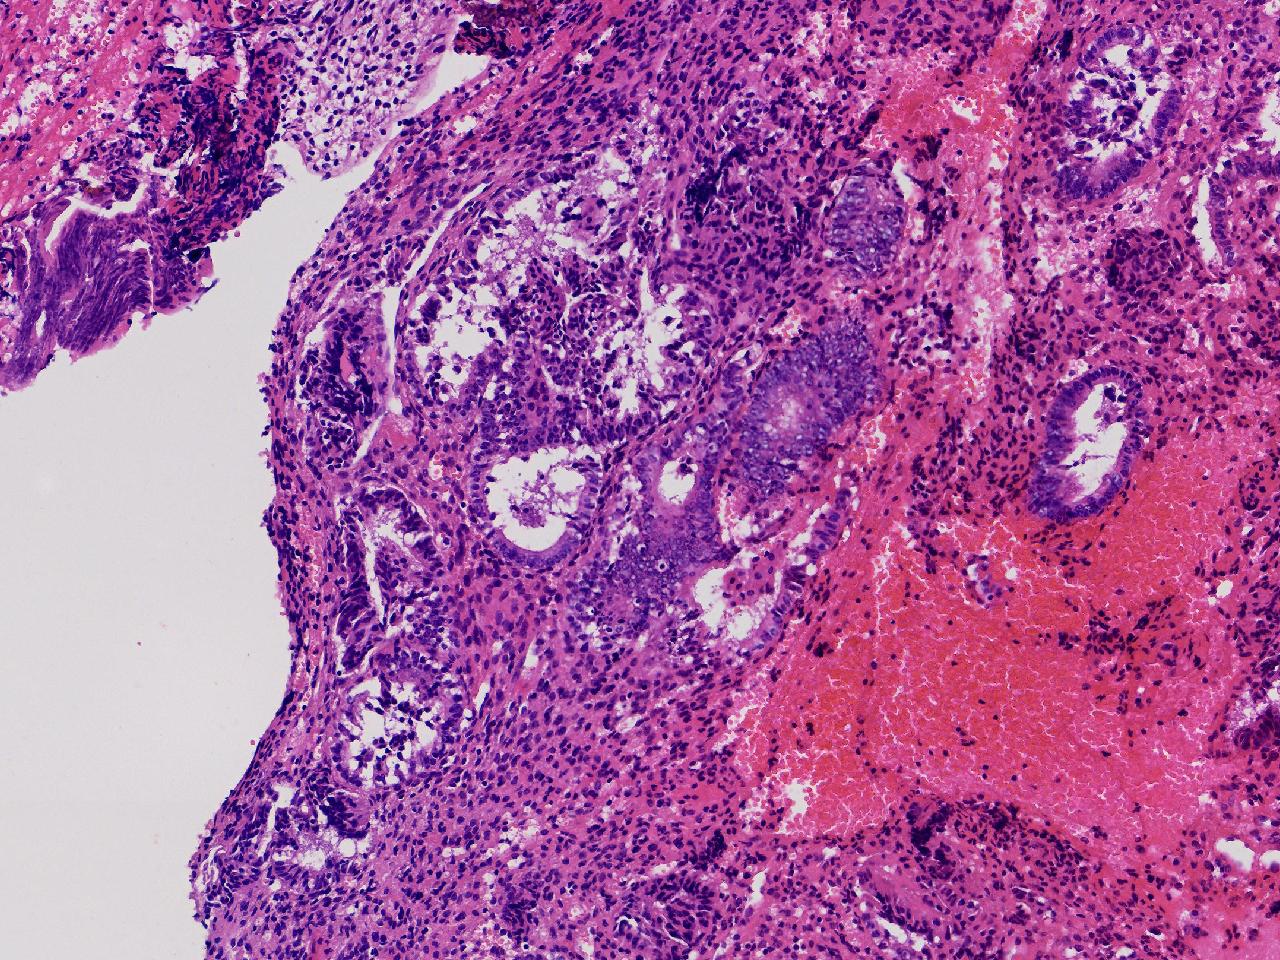

性别

女

年龄

55岁

女,55岁,月经紊乱4年,彩超示:子宫内膜增厚(内膜厚15.7mm),末次月经:2025年7月27日。

宫腔镜下子宫内膜活检

灰粉色不整形软组织多块,1.5X0.8X0.6厘米。

考虑:子宫内膜增生伴子宫内膜炎

子宫内膜增生紊乱,内膜息肉样结构